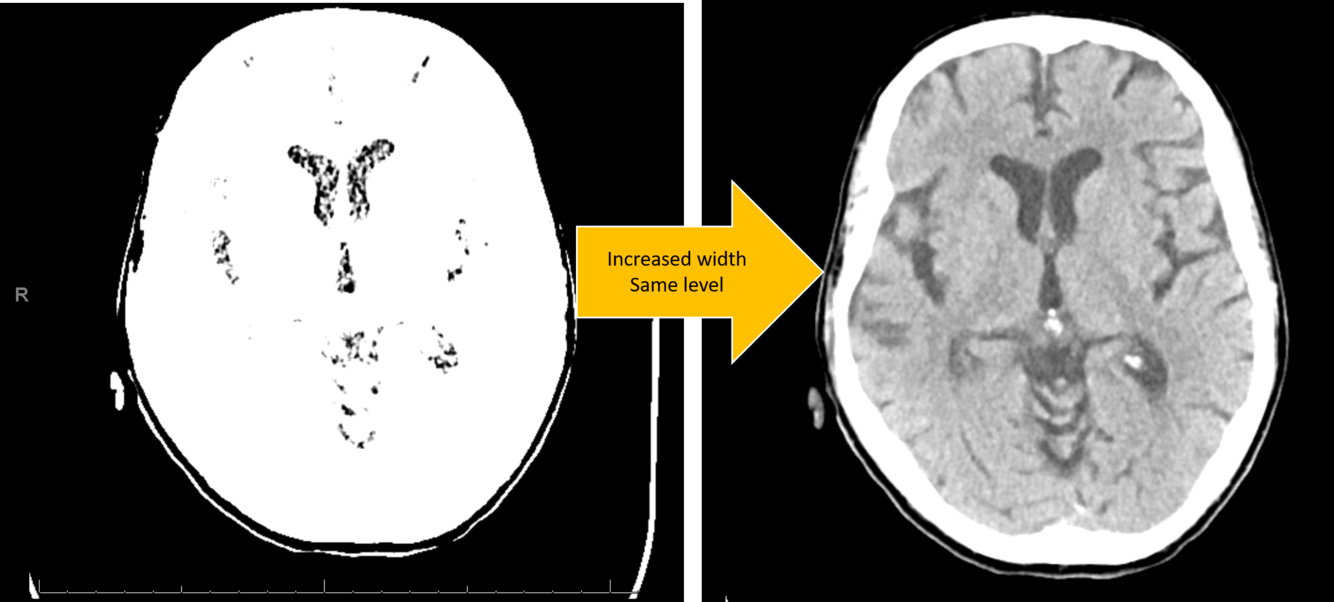

CT brain image has level of 2 HU and window of 2 HU. Altering what parameter will improve contrast?

increasing the width HU will improve contrast